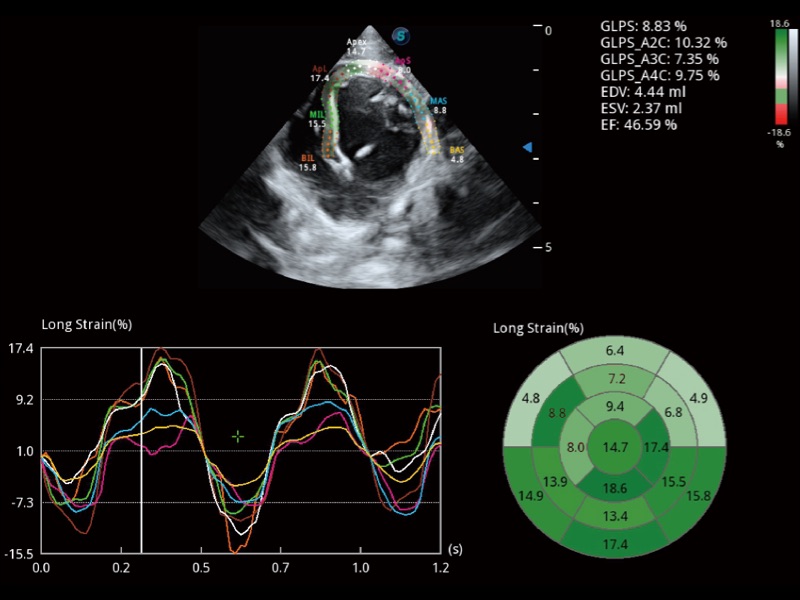

能夠基于左心室壁追蹤和辛普森法,自動(dòng)計(jì)算射血分?jǐn)?shù),支持多個(gè)可移動(dòng)點(diǎn)描跡,與手動(dòng)測量相比,極大節(jié)省了動(dòng)物醫(yī)生的時(shí)間和精力。

具備多種協(xié)議可選,同時(shí)支持17階段劃分法和專業(yè)的SE報(bào)告。